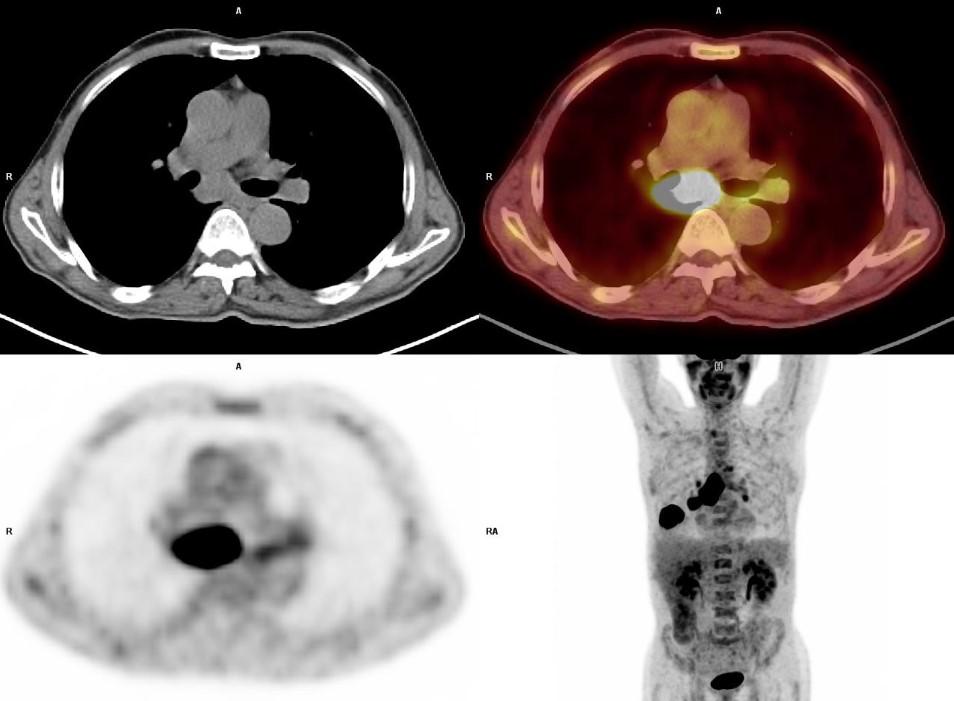

*66 years old male patient with larynx cancer.

Answer: Lung Cancer

66 years old male patient with larynx cancer. PET-CT showed a solid mass on right lung lower lobe and subcarinal enlarged lymph node with high FDG uptake. Histopathology revealed squamous cell cancer.